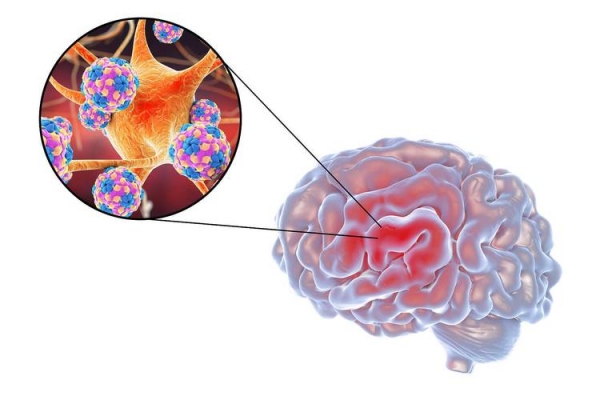

有可能病情会迅猛发展成严重肺炎以及急性呼吸窘迫,脑炎属于典型且危险的并发症,呈现出嗜睡、意识混乱、抽搐乃至昏迷的状况,幸存者也许会出现长期神经后遗症,像是性格改变以及持续抽搐。